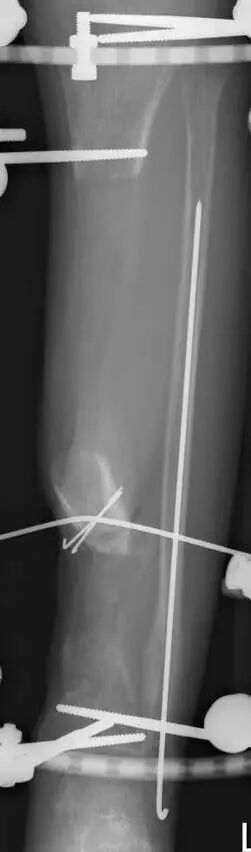

经验与教训:胫骨干骺端骨折皮下传钢板,力线有些差,内翻,但可以接受。伤口感染,如果简单换药引流也无大碍。结果用双氧水冲洗后造成肌肉坏死,胫前肌腱坏死,骨坏死外露,处理困难。最后结果还希望原作者上传,大家共同接受教训。

最后一个病例

(网友提供)最后的病例是伤后40天由外地转来。开放骨折外固定架固定,骨坏死外露,用连珠和双氧水冲洗。入院时还存在足下垂,腓神经损伤、胫后动脉损伤。